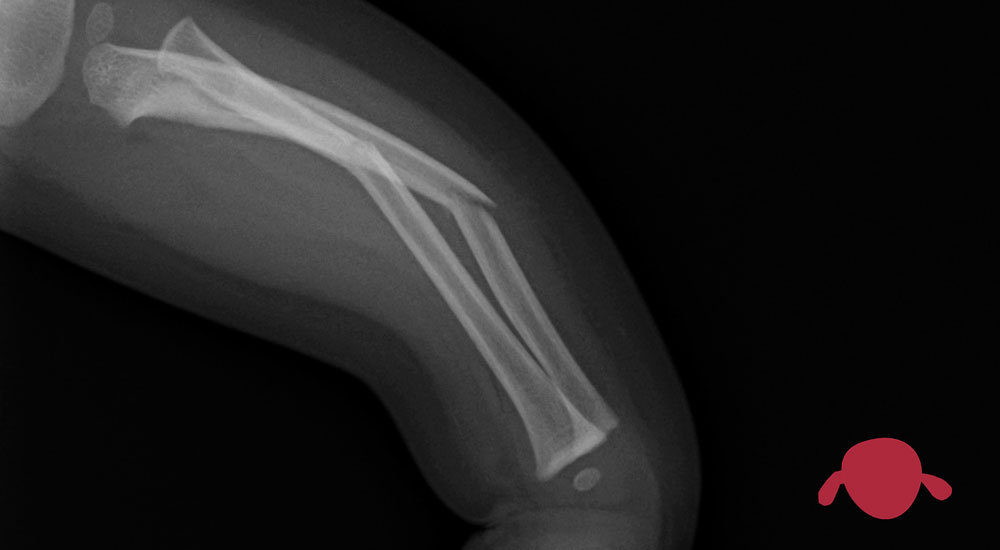

Los huesos crecen en longitud por unas zonas que están en sus extremos. Son las placas de crecimiento y los traumatólogos les llamamos “físis”. Esas físis son como discos de células madre del crecimiento de los huesos. Y vuelvo a insistir, esos discos están en los extremos de cada lado del hueso. En todos, en todas las razas. Y por supuesto que se ven claramente en la radiografía. La radiografía ve el calcio del hueso, pero ese disco de crecimiento tiene cartílago y eso es transparente a los rayos.

Así, si la fractura no pasa por esa zona de crecimiento… NO va a afectar al crecimiento. En medicina poco es 100%, pero salvo catástrofe a otro nivel, si la fractura de tu hijo no toca la fisis (la zona de crecimiento), no afectará al crecimiento de esa zona del hueso.

El hueso tras una fractura deja una cicatriz como los anillos de los árboles que se ven con un tronco cortado. Hay gente que viendo la separación entre anillos saben qué le pasó al árbol. Al hacer una radiografía , por ejemplo, 6 meses tras la lesión podemos ver una línea que se ha separado de la zona de crecimiento de manera simétrica si todo va bien (como un anillo del tronco del árbol). Y lo vemos de manera asimétrica si un lado no crece bien. En otro post os cuento qué hacer si se está produciendo un crecimiento “incorrecto” tras una fractura que afecte a la zona de crecimiento.